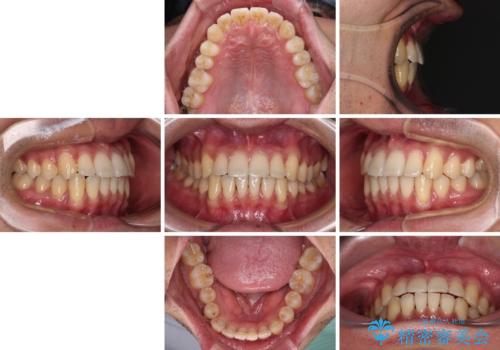

ワイヤー装置での上下前歯の部分矯正

- 上下前歯のデコボコを気にして来院された患者様です。

口元の突出感や奥歯の咬み合わせに問題がなかったため、インビザラインの廉価版パッケージを用いるか上下ワイヤー装置での部分矯正を提案しました。

部分矯正は咬み合わせが不安定になったり、スペースができてしまったりと、適用となる患者様は極めて限られますが、こちらの方はスムーズに治療を終えることができました。